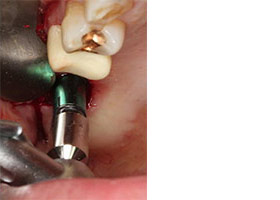

植牙合併無敲擊水壓式上頷竇增高術